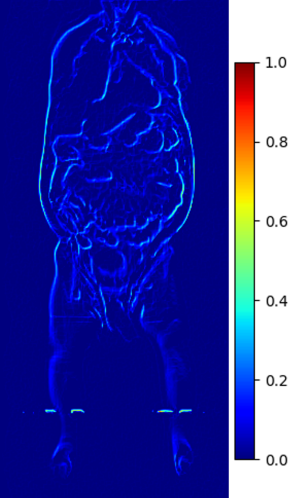

B.1 Fat Validation

We ran further experiments to investigate whether the generated MRIs preserve fat information. We use an image-based regression network trained on the UKBiobank to estimate DXA metadata information from 2D compressed middle coronal and sagittal MRIs [35]. Pearson’s correlations using Equation 8 comparing reference values and generated values are reported in Figure 17 with most fields having high correlation . We show that the generated MRIs preserve crucial internal information.

B.3 Preservation of Spine Curvature and Fat

For the spine segmentation on UK Biobank, we use a UNet++ model [81] with Dice Loss. We use a model trained to predict curves on DXA on UK Biobank [9]. We show in Figure 20 that generated MRIs preserve the spine curvature from normal to severe scoliosis cases. We also study the case when DXA is used to generate the MRIs and show in Figure 14 how the correlation to real curvatures compares to the input MRI case. The curvatures of the MRI generated from the coronal plane match the DXA curvatures more than the curvatures generated from sagittal MRI. This is expected since the antero-posterior plane of DXA is equivalent to the coronal plane for MRIs. This also explains the greater Pearson’s correlation coefficient of the coronal MRI (0.89) and DXA-generated curvature (0.88) compared to sagittal-generated curvature (0.87) relative to the reference curvature on the coronal plane. We observe though that MRI generation using X-Diffusion from another plane than the conventional plane for scoliosis assessment is valid.

For the spine segmentation on UK Biobank, we use a UNet++ model [81] with Dice Loss. We use a model trained to predict curves on DXA on UK Biobank [9]). We measure the Pearson correlation factor [9] of spine curvature measured on the generated MRIs where the input is a single MRI coronal slice, a single sagittal slice, or from the paired DXA, against the curvature of reference real MRIs of the same samples. The correlation coefficients are 0.89 for the coronal MRIs, 0.88 for the sagittal MRIs, and 0.87 for the DXAs on the test set of 308 human-annotated angles. We can then bin the curvature, , of the spines under different scoliosis categories based on human-annotated angles: mild: , moderate: , and severe . We show the results in Figure 20. This illustrates that the generated MRIs preserve the spine curvature from normal to severe scoliosis cases.